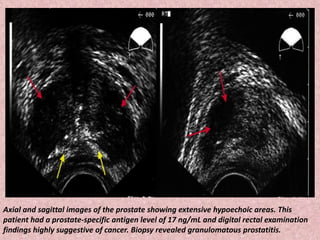

Axial and sagittal images of the prostate showing extensive hypoechoic areas. This

patient had a prostate-specific antigen level of 17 ng/mL and digital rectal examination

findings highly suggestive of cancer. Biopsy revealed granulomatous prostatitis.